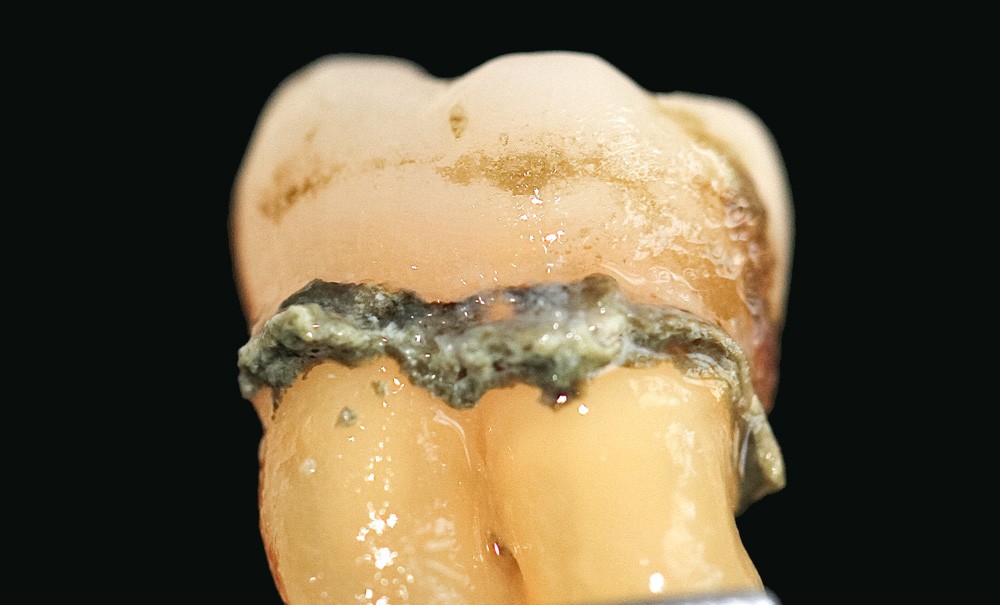

Le but de cette revue narrative illustrée est de rappeler et de montrer l’importance de la spécificité du tartre sous-gingival, présent dans les poches parodontales.

La bonne connaissance de son mécanisme de formation associée à l’inflammation d’une part, et de ses mécanismes d’adhésion en rapport avec l’anatomie radiculaire d’autre part, est un guide pour réaliser un traitement cohérent et choisir l’instrumentation adéquate. Cela permet aussi de discuter du paradoxe entre les résultats cliniques, souvent satisfaisants, et les observations microscopiques des dents extraites, montrant la présence de tartre après l’instrumentation sous-gingivale.

Le tartre sous-gingival est probablement le produit, plutôt que la cause, des poches parodontales. La plaque déclenche une inflammation gingivale, qui conduit à la formation de poches, générant un environnement idéal pour l’accumulation de plaque et la formation de tartre. Mais, à son tour, le tartre sous-gingival est un facteur responsable de la chronicité et de la progression de la maladie parodontale. Le tartre est un facteur de rétention bactérienne, et la nature des cristaux qui le composent aurait un effet cytotoxique sur les cellules épithéliales [3].